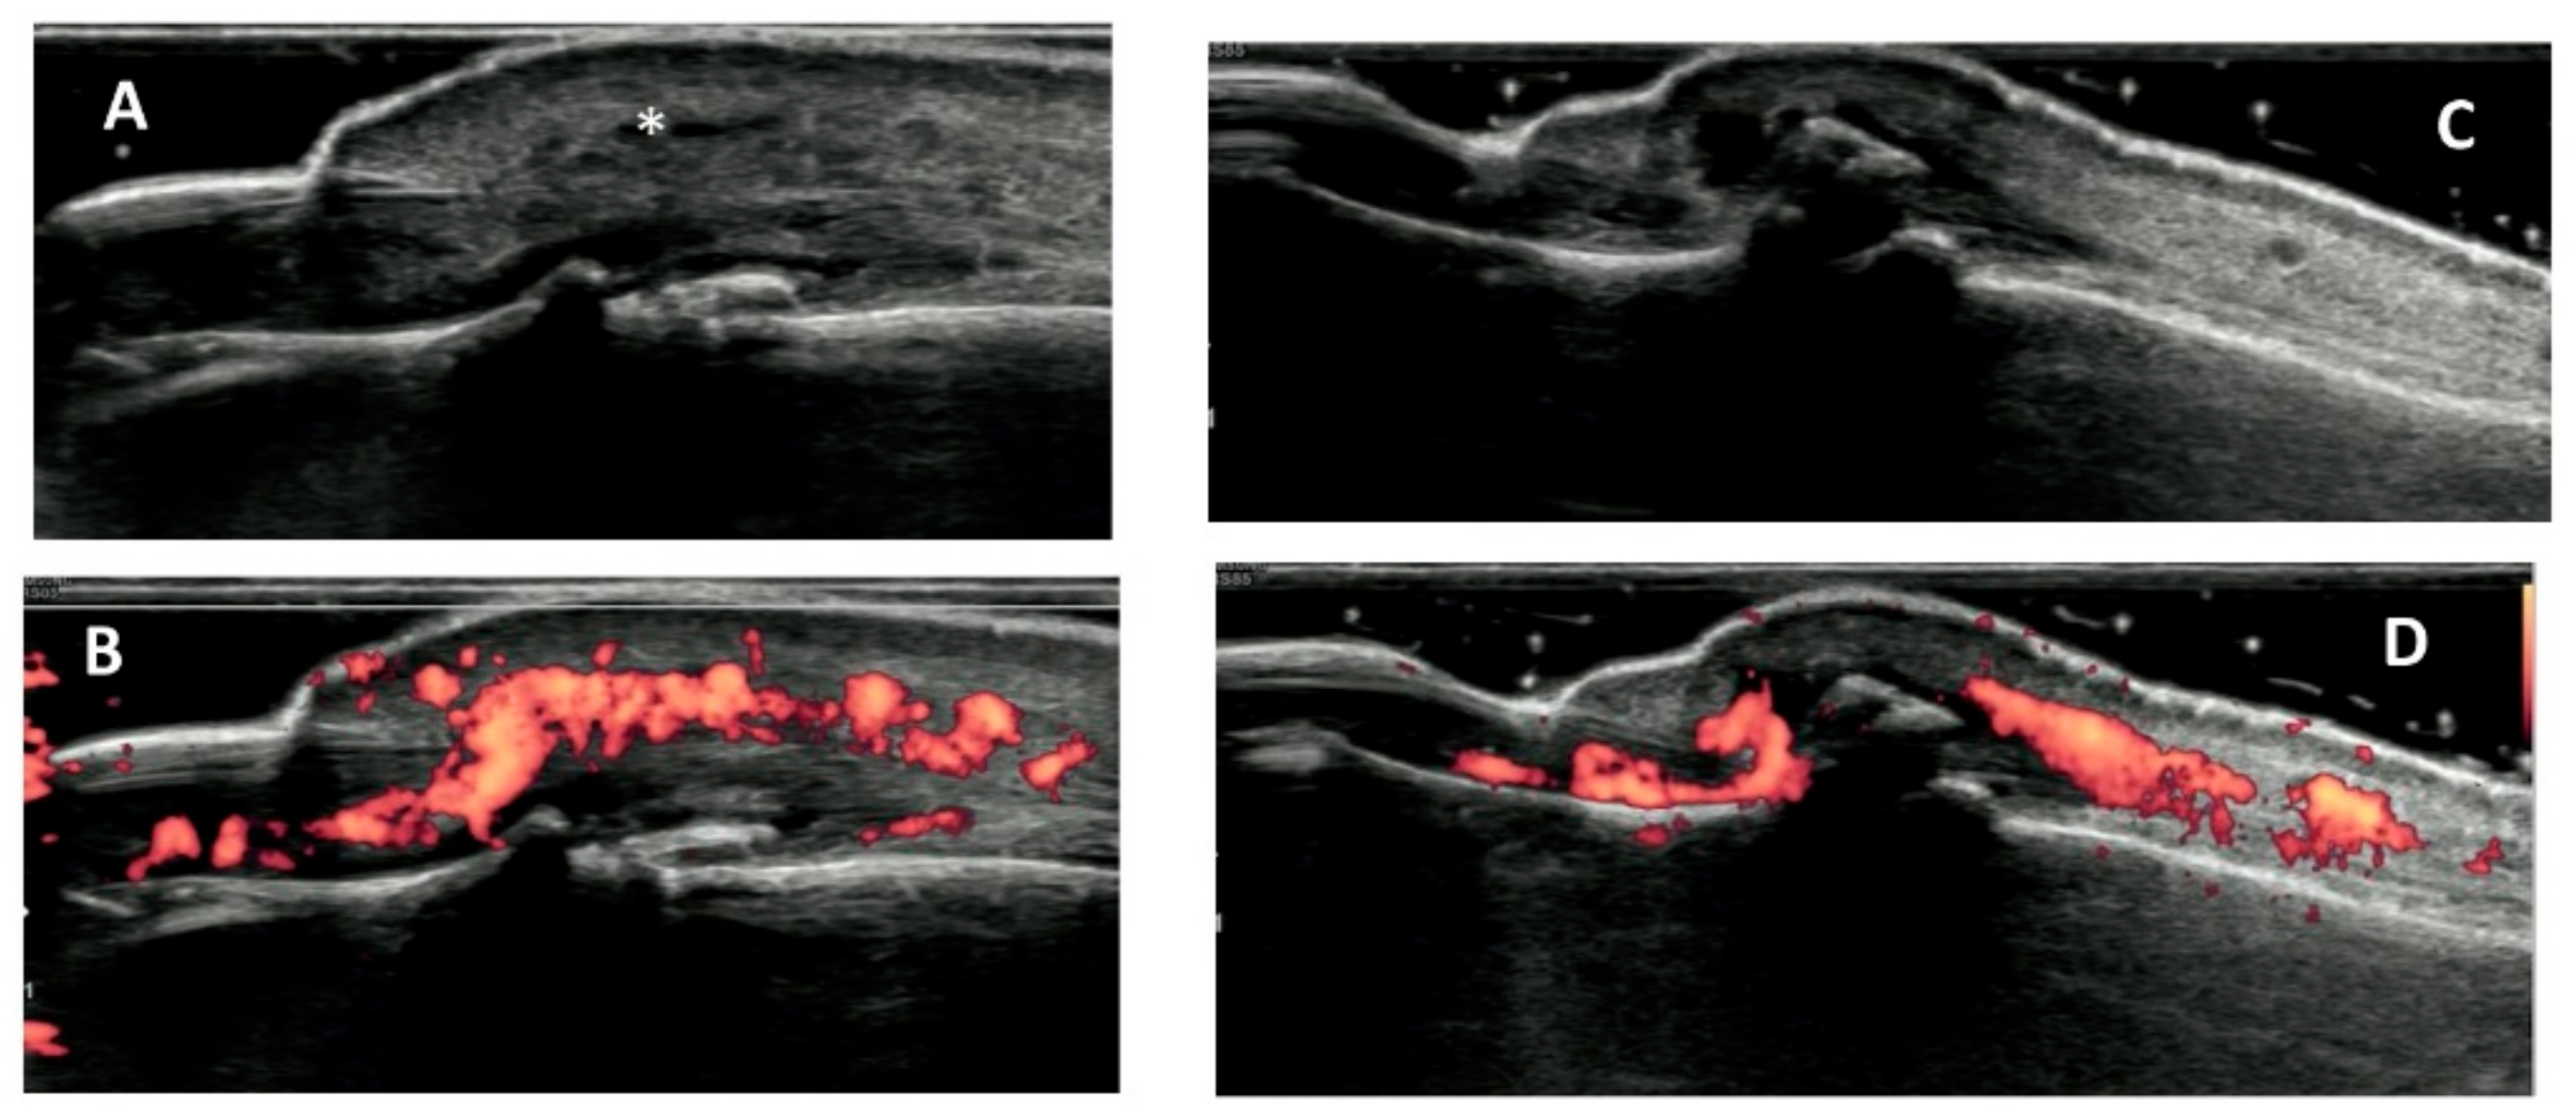

- Vlychou, M.; Koutroumpas, A.; Malizos, K.; Sakkas, L.I. Ultrasonographic evidence of inflammation is frequent in hands of patients with erosive osteoarthritis. Osteoarthr. Cartil. 2009, 17, 1283–1287. [Google Scholar] [CrossRef]

- Kaeley, G.S.; Bakewell, C.; Deodhar, A. The importance of ultrasound in identifying and differentiating patients with early inflammatory arthritis: A narrative review. Arthritis Res. Ther. 2020, 2, 1–10. [Google Scholar] [CrossRef] [PubMed]

- Dubash, S.R.; De Marco, G.; Wakefield, R.J.; Tan, A.L.; McGonagle, D.; Marzo-Ortega, H. Ultrasound Imaging in Psoriatic Arthritis: What Have We Learnt in the Last Five Years? Front. Med. 2020, 25, 487. [Google Scholar] [CrossRef]